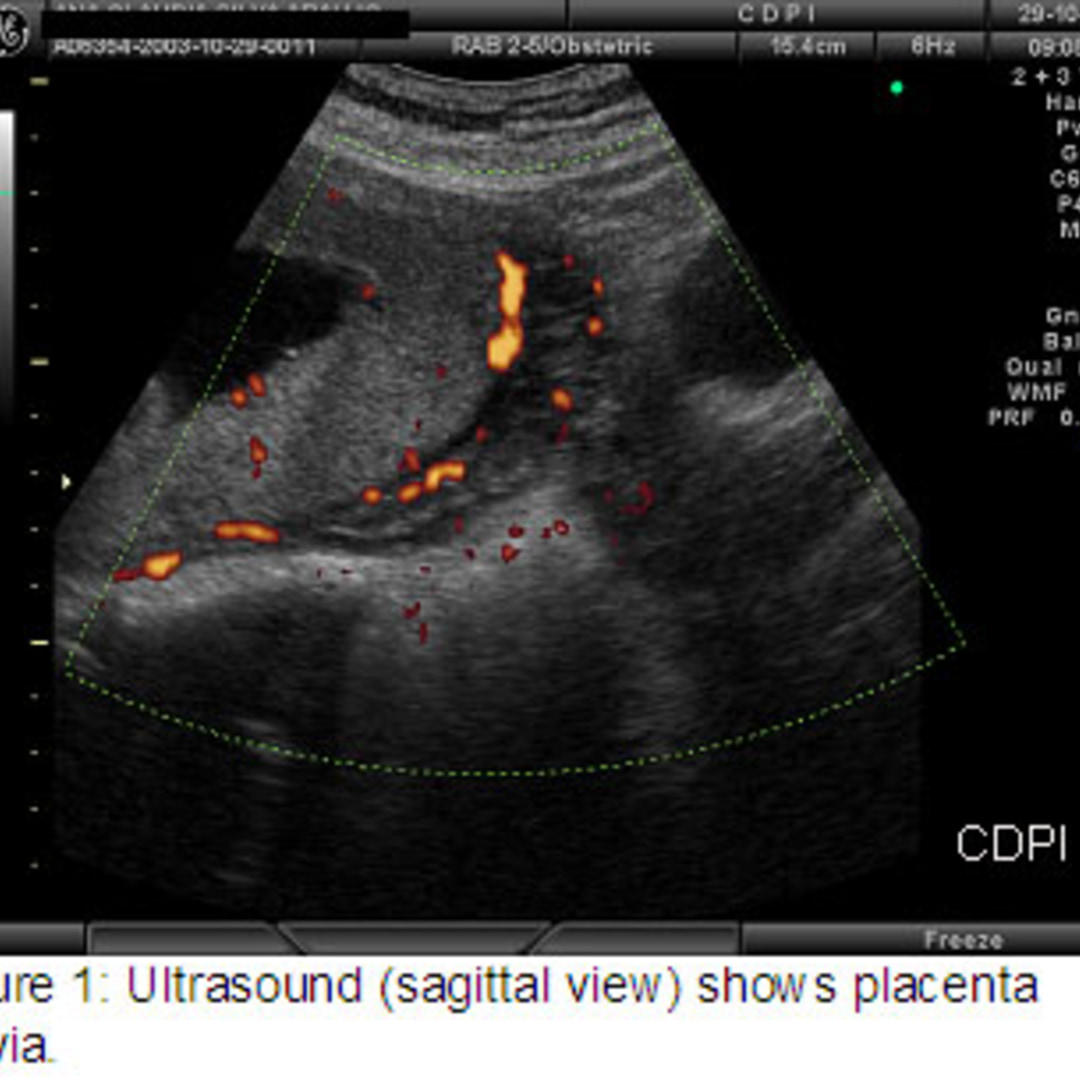

Spectrum of placenta previa. (a) Transvaginal US image obtained at ...

11.4: Placenta Previa - Medicine LibreTexts

US Pregnancy - Placenta - Complete placenta previa